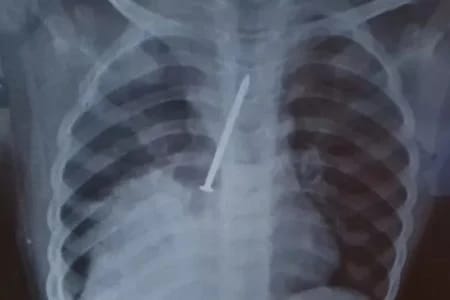

Insatisfeitos, os pais da criança resolveram fazer um exame raio-x particular. Foi quando identificaram a gravidade do problema do filho, que foi transferido para o Hospital Geral do Estado (HGE), onde o garoto passou por uma cirurgia, mas não resistiu.